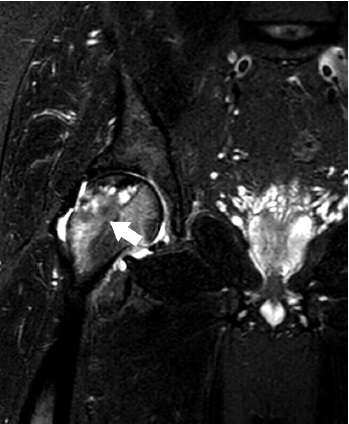

In the main group, despite the persisting trabecular oedema, integration and pronounced remodeling of the bone autograft at the site of its impaction were observed (Fig. 13).

Fig. 13. MRI of the left hip joint 12 months after the closed combined autografting of the femoral head; no pathologic changes in the femoral head, moderate trabecular oedema in the area of the muscle autograft is observed (indicated by arrows)